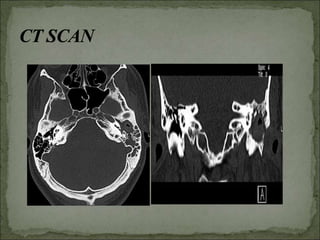

X-ray mastoids & CT temporal. Attic

and antrum destruction caused by

cholesteatoma best seen lateral in CT.

C/S of eardischarge. Tuning fork test Audiogram X-ray mastoids & CT temporal. Attic and antrum destruction caused by cholesteatoma best seen lateral in CT. 43